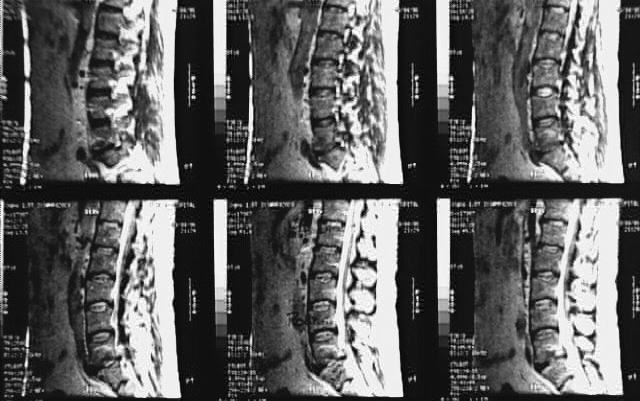

Back- Lumbar Spine MRI Sagittal 1